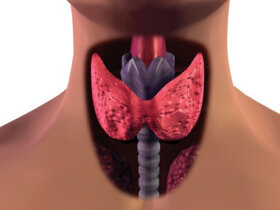

갑상선 이상 증상을 조기에 발견하는 것은 아주 중요하다.

우리는 갑상선 기능 저하증과 갑상선 기능 항진증, 이 두 가지 질병에 익숙하다. 하지만 이 두 질병이 어떤 차이가 있는지 알고…